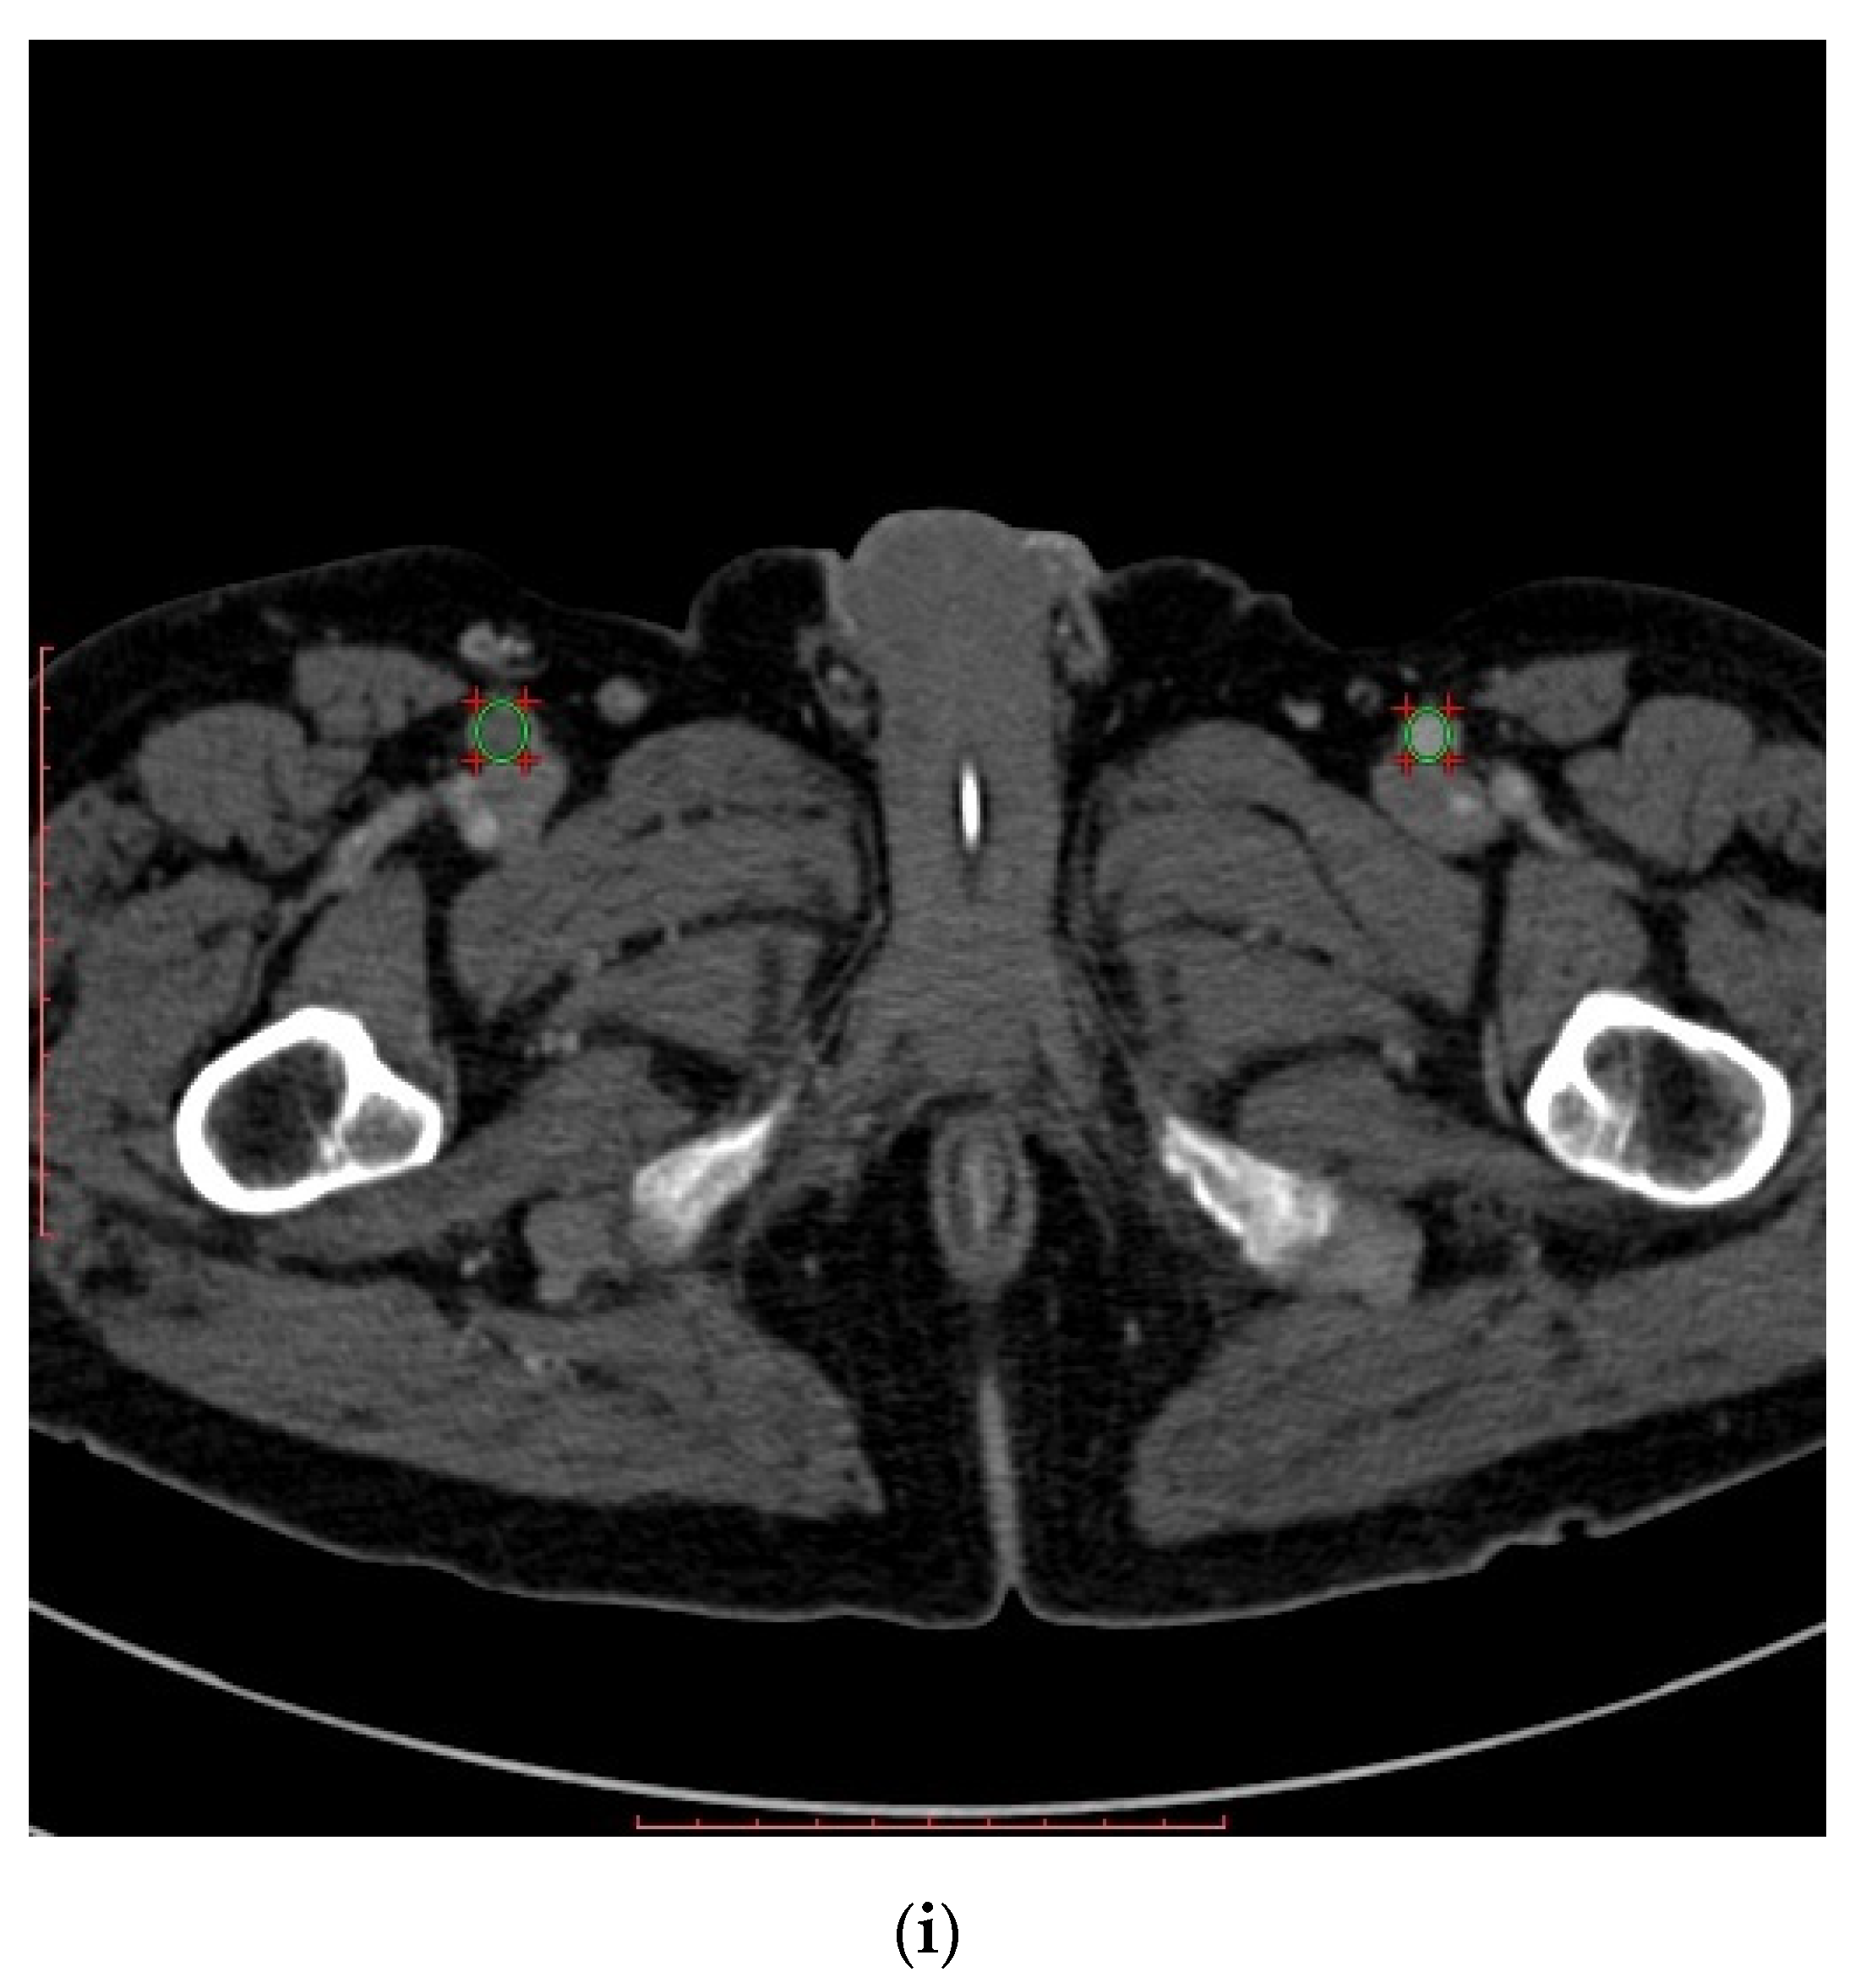

Figure 1.

Computed tomography angiography images: (a) dilation of the right and left pulmonary arteries with a borderline width of the pulmonary trunk; (b) left pulmonary artery filling defect suggesting presence of embolic material; (c) non-uniform aortic density suggesting acute aortic syndrome; (d) aneurysm of the ascending aorta, aortic arch and proximal part of the descending aorta; (e) aortic aneurysm with massive parietal thrombi/aortic aneurysm with chronic dissection and clotting of the supposedly dissected canal; (f) angular (Gothic) aortic arch; (g) stenosis of the proximal section of the superior mesenteric artery; (h) occlusion of the proximal section of the right superficial femoral artery; (i) filling defects in the veins of the right iliac axis that is most probably a thrombotic material.

On the basis of the aortic image on CTA of the pulmonary arteries and life-threatening condition, the decision was made to supplement diagnostics with CTA of the thoracic-abdominal aorta. CTA of the aorta showed aneurysm of the ascending aorta, aortic arch and proximal part of the descending aorta (maximum diameters of 6.0 cm, 3.9 cm and 4.9 cm, respectively) (Figure 1d). From the level of the left subclavian artery (LSA) origin over the further part of the thoracic aorta and proximal abdominal aorta, to the level of about 2.5 cm below the renal arteries origin, the vessel periphery revealed the presence of wide hypodense structure with thickness up to 1/2 diameter of the aortic lumen; in the proximal section, the structure was located medially and posteriorly, then left-sided and posteriorly, and in the distal section it was located both left-sided and anteriorly (Figure 1e). Regarding differentiation, the CTA image of the aorta could correspond to aortic aneurysm with massive parietal thrombi/aortic aneurysm with chronic dissection and clotting of the supposedly dissected canal. Moreover, CTA revealed angular (Gothic) aortic arch (Figure 1f), short-segment stenosis of the proximal section of the superior mesenteric artery by 50–70% of the lumen (Figure 1g), occlusion of the proximal section of the right superficial femoral artery (Figure 1h) and filling defects in the veins of the right iliac axis that is most probably a thrombotic material (Figure 1i).